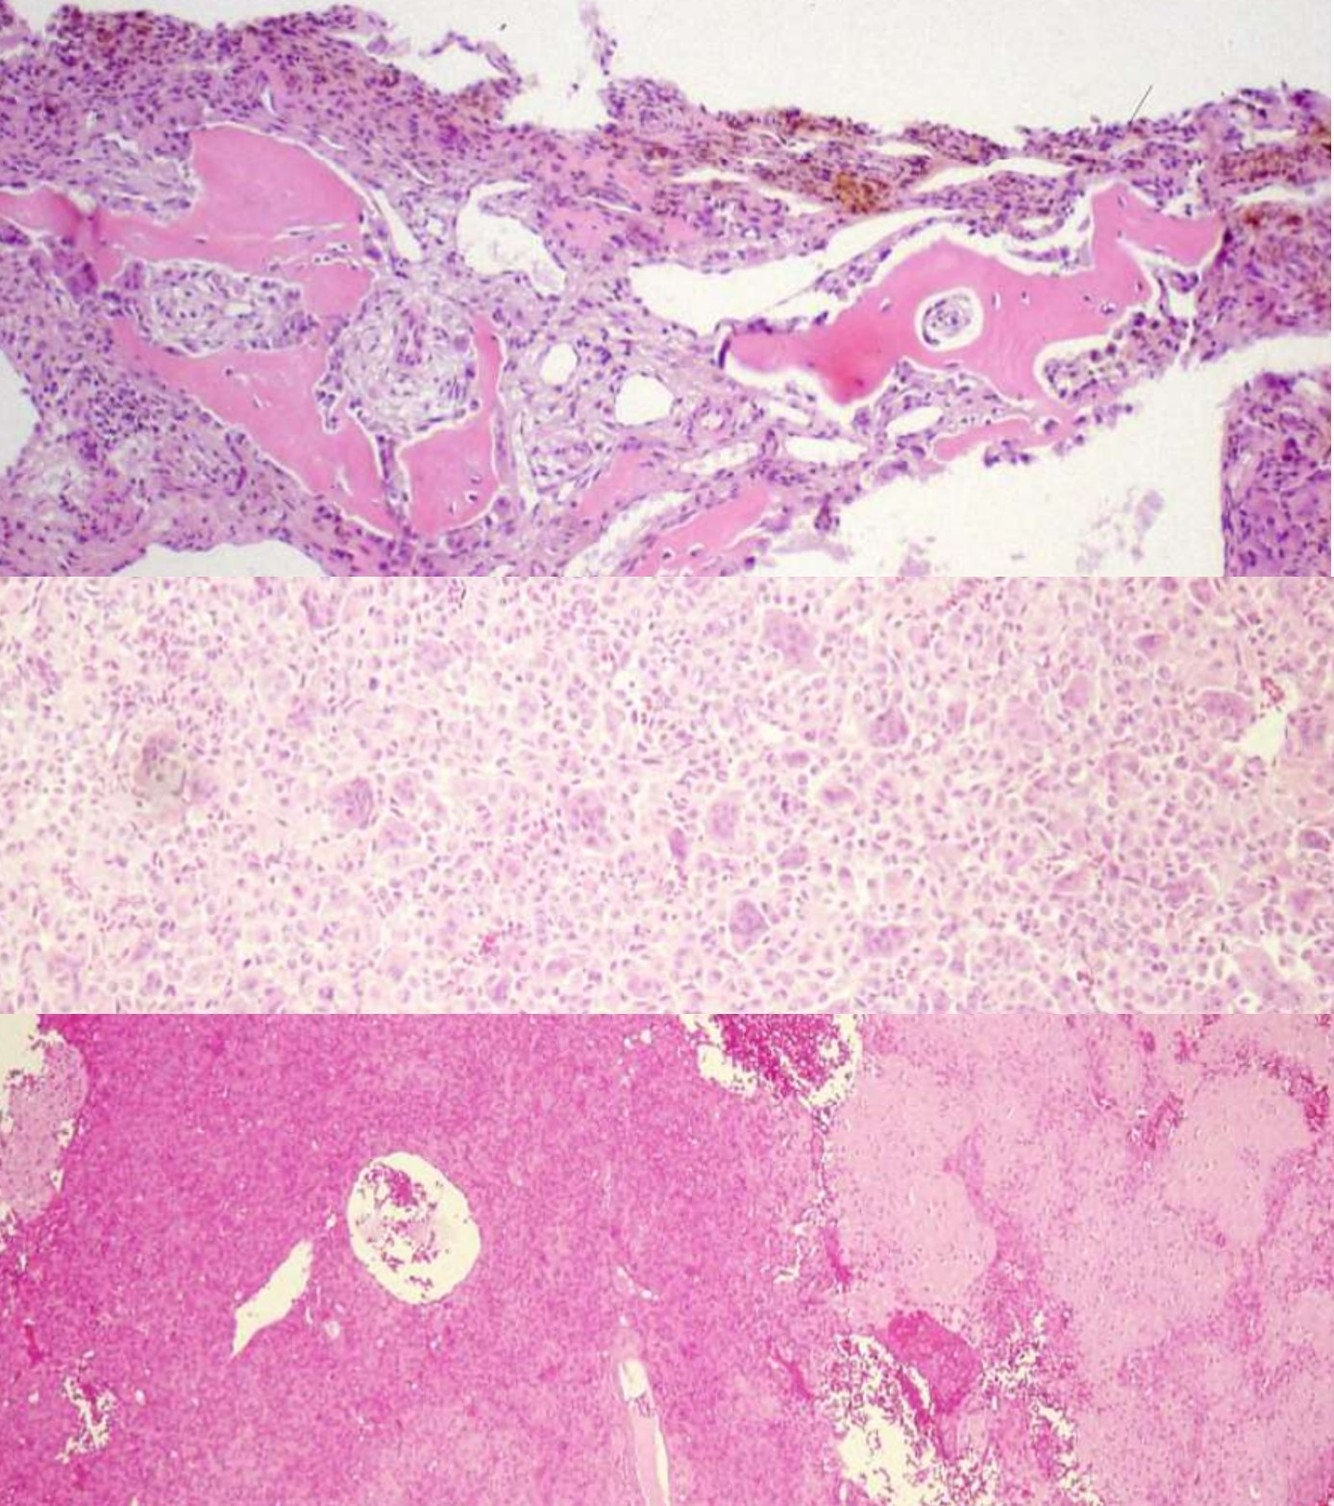

OSTEOCHONDROMA

ENCHONDROMA

CHONDROBLASTOMA

CHONDROMYXOID FIBROMA